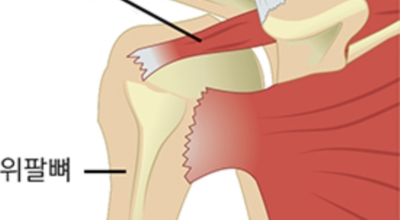

회전근개파열이란?

회전근개 증후군은 회전근개에 변형과 파열이 생긴 질환을 말해요. 회전근개란 어깨와 팔을 연결하는 4개의 근육(극상근, 극하근, 소원근, 겹갑하근) 및 힘줄로 이루어져 있는 것으로 보입니다. 어깨 근육통을 막연히 오십견으로 알고 방치하다가 치료 시기가 늦어지는 경우가 있답니다. 적절한 시기에 병원에 가는 것이 필요해요.

어깨 회전근개 파열은 부분 파열에서 전층 파열, 소파열에서 대파열로 병이 진행하는 성향이 있는데, 파열의 부위가 넓다고 하여 (진행 정도가 크다) 통증이 심각해지진 않습니다. 그렇기에 부분 파열이어도 통증이 심각할 수도 있다고 하며 전층 파열이어도 통증이 경미할 수 있기 때문에 증상이 병의 진행 정도를 확인하는 척도가 되진 않습니다.